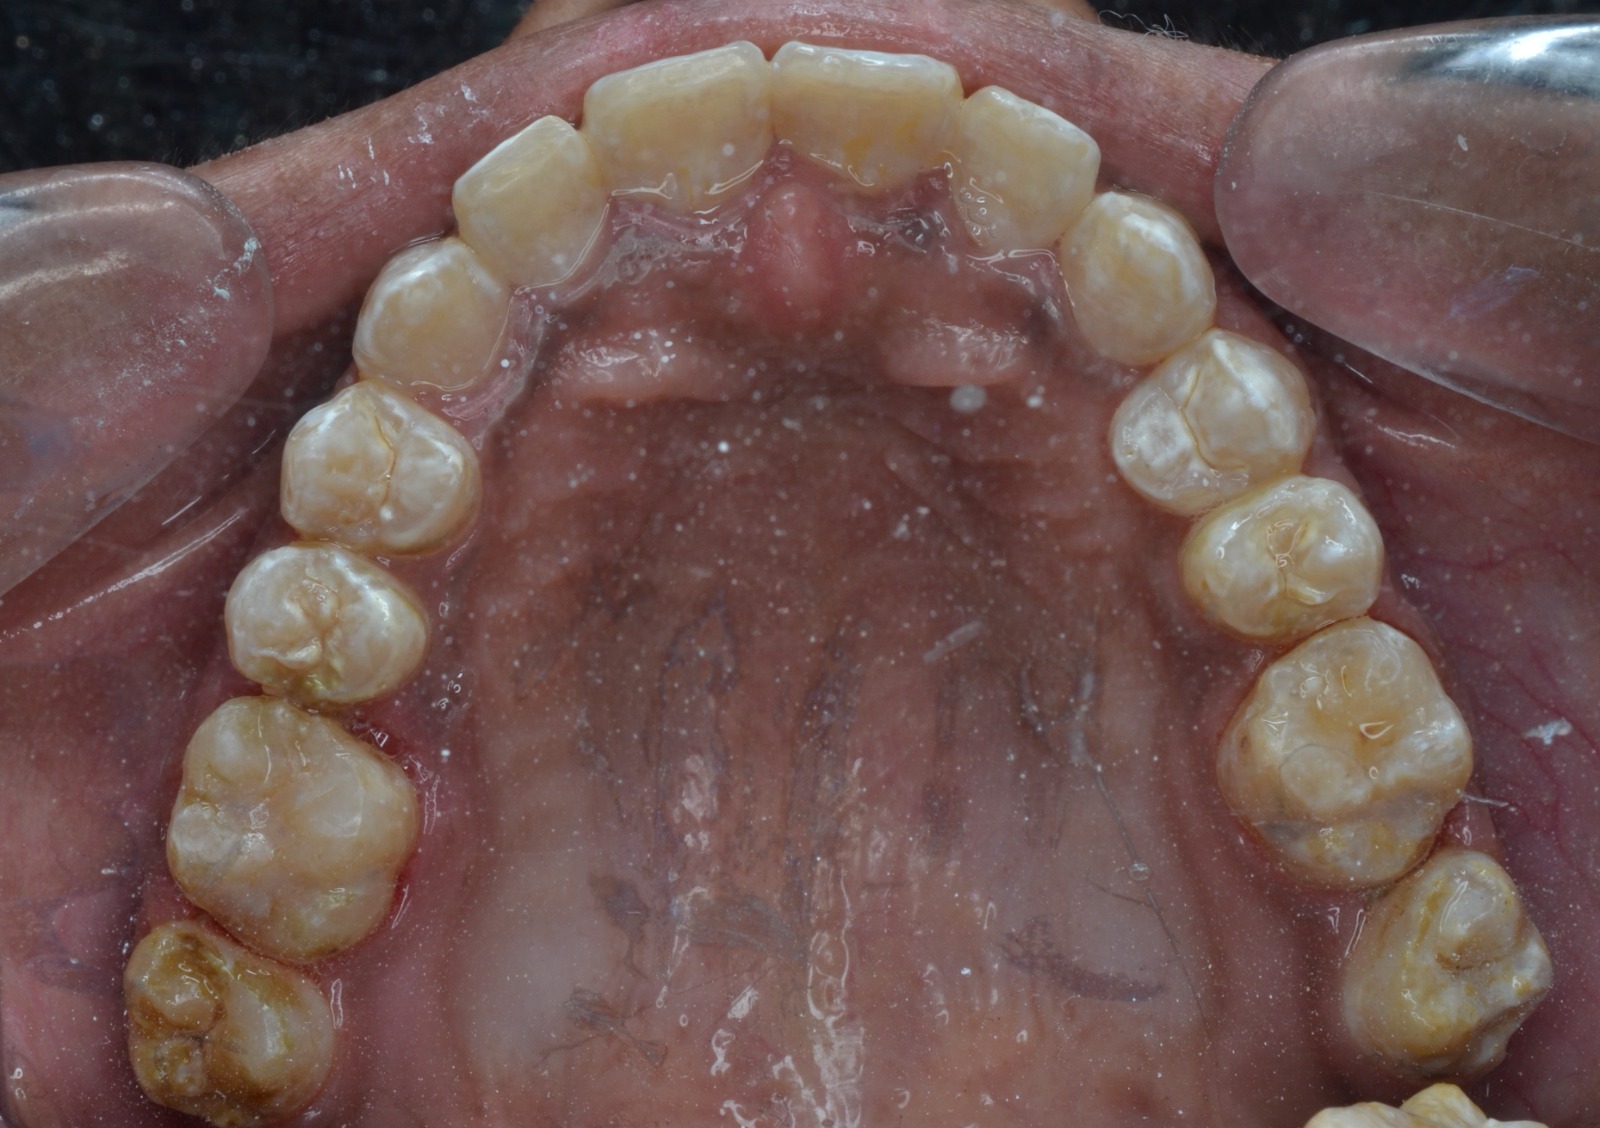

Sairam dental care located in Dharmapuri, with Leading Dentist In Oddapatti, is the Dental Hospital with exclusive root canal, Braces & Invisalign center. Led by renowned Drs Raghuraaman ( Periodontist) and Nivetha Raghuraaman ( Orthodontist) Sairam dental care offers gum treatment with expertise in laser, root canal treatment and digital smile correction with advanced technology aim to focus on aesthetics, comfort and precision. The clinic also specializes in Invisalign treatment, digital smile makeover, laser gum care, dental implants, root canal therapy, extractions and full-mouth rehabilitation blending compassionate care and clinical excellence.

Our professional, experienced, and passionate dentists make us the best choice for Invisalign treatment in Dharmapuri, providing top-notch dental services.